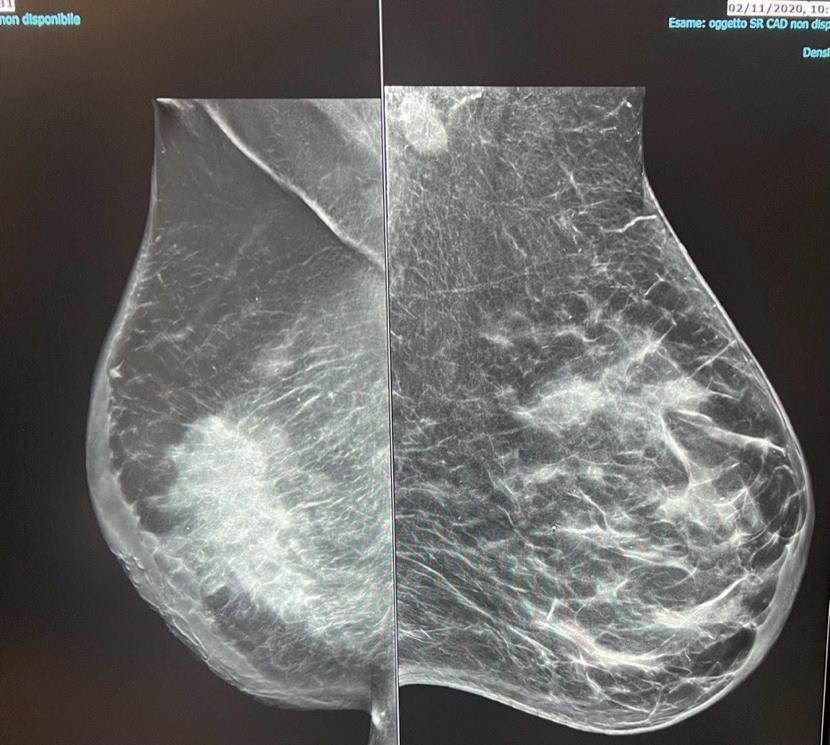

Si descrive il caso di una paziente di 68 anni, non fumatrice, con performance status ECOG 0. In anamnesi un intervento di splenopancreasectomia nel 2011 per un carcinoma pancreatico ed una fibrillazione atriale parossistica diagnosticata nel 2016. Come terapia a domicilio si segnala assunzione di dabigatran e flecainide in relazione alla suddetta comorbilità cardiologica. In seguito al riscontro autopalpatorio di nodularità alla mammella sinistra, effettua approfondimenti strumentali con ecografia mammaria e mammografia, seguiti da agobiopsia con riscontro di carcinoma mammario duttale infiltrante di origine mammaria. Viene pertanto sottoposta nel 2016 a mastectomia sinistra con biopsia del linfonodo sentinella. All’esame istologico si descrive un carcinoma mammario duttale infiltrante con recettori ormonali positivi (ER 90% PgR 10%), HER2 1+ con un Ki-67 del 20%. Dopo l’intervento chirurgico veniva impostata una terapia endocrina con letrozolo per una durata teorica di 5 anni. A Maggio 2020, quindi ancora in corso di letrozolo, la paziente riscontra un nodulo parasternale all’autopalpazione. Viene pertanto richiesta una TC di stadiazione che conferma la presenza del nodulo parasternale di 21 mm di diametro massimo ed un linfonodo ascellare sinistro di 14 mm. Eseguiva quindi una biopsia ecogui-

Dopo soli 4 mesi, alla prima rivalutazione con TC Totalbody, si evidenziava una progressione epatica di malattia. Alla luce della rapida progressione si decideva di effettuare una nuova ricaratterizzazione di malattia tramite biopsia di lesione epatica. L’esame istologico deponeva per carcinoma duttale infiltrante ER 95%, PgR 15%, Ki-67 45%, HER2 positivo (IHC 3+).